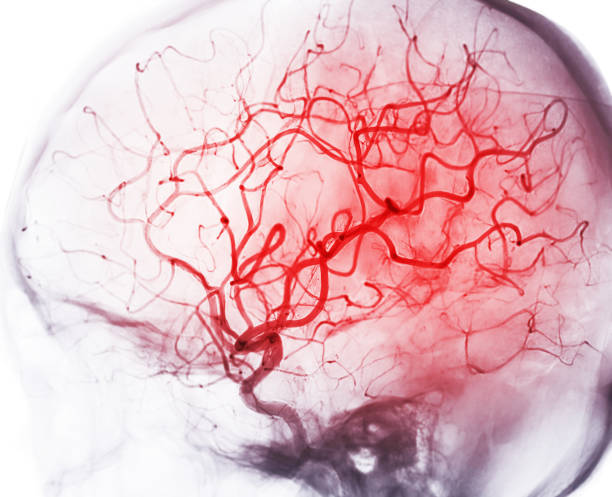

23년 국제 뇌졸중학회(International Stroke Conference 2023)에 발표된 연구에 따르면, 구강 건강 상태가 뇌 건강에 상당한 영향을 미치는 것으로 확인되었습니다.

해당 연구는 2014~2021년 사이에 뇌졸중 병력이 없는 성인 약 4만명을 대상으로 진행된 대규모 연구로, 연구진은 구강 건강과 뇌 건강 사이의 잠재적 연관성을 조사하기 위해 구강 건강에 영향을 미치는 105개의 유전적 변이를 분석하였습니다.

분석 결과, 유전적으로 구강 건강이 좋지 않은 사람들의 뇌의 미세 구조 손상이, 구강 건강이 좋은 사람들보다 43% 높은 것으로 나타났습니다.

또한, 유전적으로 충치가 발생하거나, 치아가 없거나, 의치가 필요한 사람들은 Brain MRI에서 뇌 백질의 고강도 양이 24% 증가했는데, 이는 뇌혈관 질환 발생 확률이 더 높다는 것을 의미합니다.